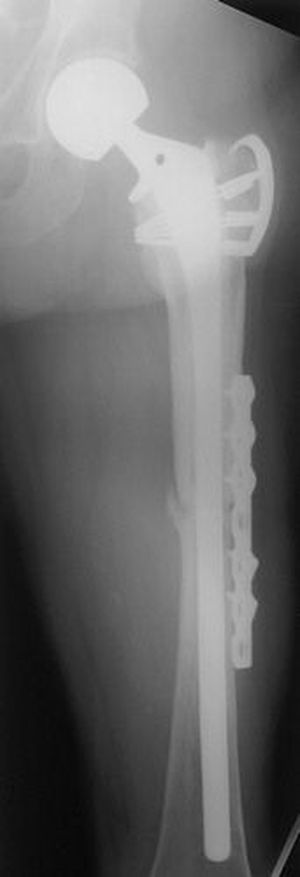

Greater trochanter clamp. Frontal radiograph shows the greater trochanter, which is attached to the proximal femur by a clamp, and a unipolar hip hemiarthroplasty. A subsequent periprosthetic fracture through the femoral midshaft was transfixed with a reconstruction plate.